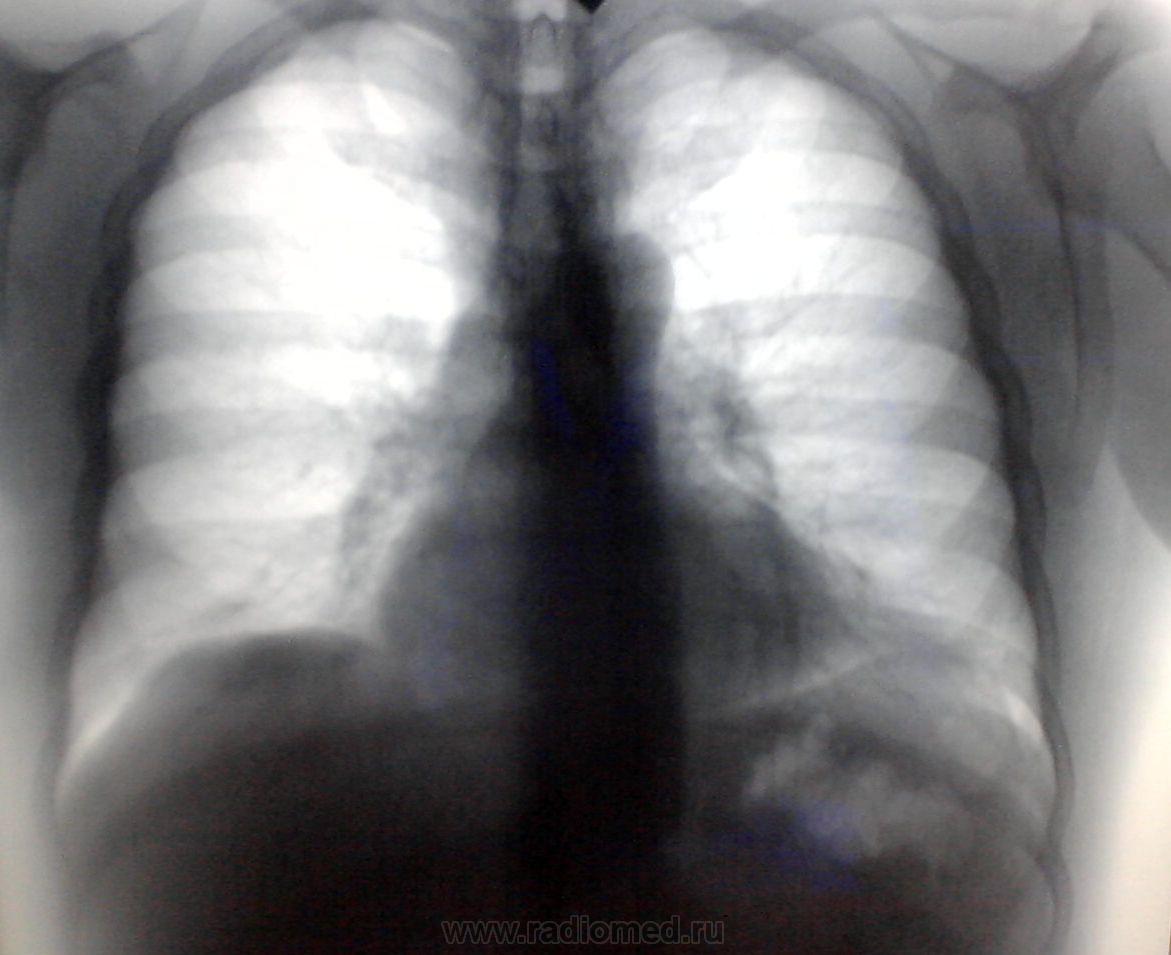

Мужчина 1973 г.р. Гиперстеник. Жалоб не предъявляет. Можно ли расценить затемнение в переднем кардиодиафрагмальном углу слева как абдоминомедиастинальную липому или есть ещё какие-нибудь варианты?( всегда это левый передний кардиодиафрагмальный угол вызывает затруднения!)

Вот снимкм.